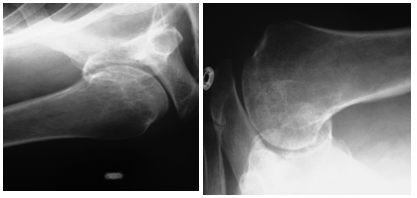

The interval between injury and surgery was around 4.5 (range 0-9) days; 33 (84.61%) patients were operated in a weeks’ time. The duration of external fixation removal was 48 (range, 39-56) days. The time to radiological union took almost 12 (range 9-14) weeks. The follow-up period was 14 months (range, 12-18). Reduction was good and maintained (Almost anatomical reposition of fragments) in 22 (56.41%) patients and fair in 17 (43.58%) patients with a reasonable alignment of opposing fracture fragments. 7 (17.94%) patients had pin tract infections during course of external fixator application and were managed appropriately till healing. 2 (5.12%) patients developed avascular necrosis of head of humerus starting after 6 months of injury. The function of shoulder was done according to the Shoulder Constant Score (C Constant and Murley). The shoulder function was found excellent in 16 (41.02%) patients, good in 14 (35.89%), moderate in 5 (12.82%) and poor in 4 (10.25%) patients. One (2.56%) patient had early inferior subluxation of gleno humeral joint which required frame readjustment despite initial good reduction. This was probably due to complex nature of the four part fracture dislocation (Figure 10).

Figure 10 The patient with post traumatic avascular necrosis of femoral head – There was collapse of humeral head along with poor shoulder function.

Complications of this complex injury are common despite employing best of the open treatment and even with non-operative management. Those leading to poor patient outcome is avascular necrosis, stiffness of the shoulder and Malunion.26-28 2(5.12%) of our patients developed avascular necrosis of humerus head. One patient was moderately pain free and another patient had constant and prolonged pain, which caused stiffness of shoulder, affecting activity of daily living after first six months of treatment, which gradually improved to some extent without any active surgical intervention. These two patients with humeral head osteonecrosis however showed clinical and radiological improvement after six months, suggesting a fact that revascularization of head of humerus might be due to creeping substitution, especially since shoulder is a non-weight bearing joint. Open surgical techniques, reduces the incidence of Malunion, but increases chances of surgical site infection, avascular necrosis of humeral head due to stripping, iatrogenic neurologic or vascular injury and implant or hardware failure.29-32 We had pin track infection in seven (17.94 %) patients, which was considered high, but the fixator was kept because it offered stability to fracture fragments and patients were treated appropriately. The benefits of closed reduction and external fixation of this complex proximal humerus fracture by external fixation and stabilization apparently overweigh these minor undesirable complications during the course of treatment.